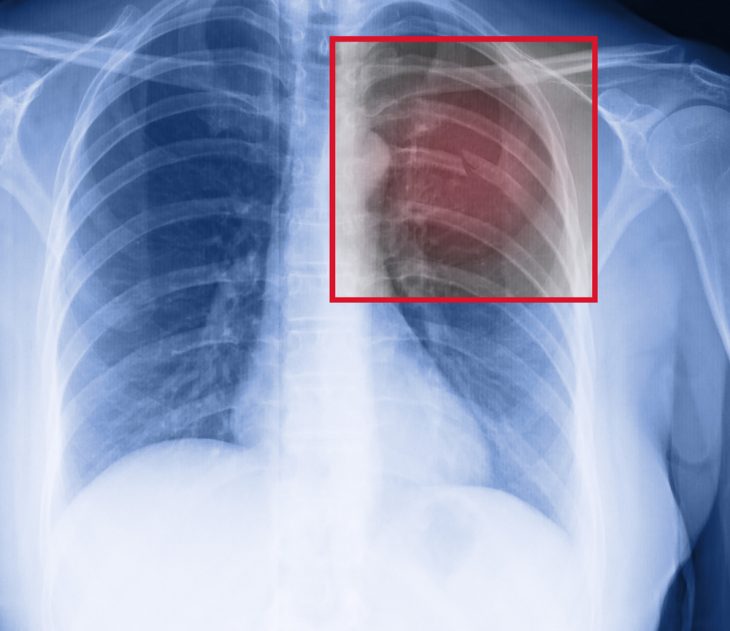

Особую опасность несут передние двусторонние и левосторонние переднебоковые «окончатые» переломы. Они вызывают маятниковые колебания сердца и крупных сосудов в процессе дыхания, что приводит к нарушению сердечной деятельности. Вот как выглядят такие дефекты.

Травматический пневмоторакс. Служит неоспоримым признаком разрыва легкого отломками ребра. Характеризуется накоплением свободного воздуха между листами плевры. Воздух закачивается с каждым вдохом, давит на диафрагму, опускает ее вниз, оттесняет средостение вместе с сердцем и сосудами в противоположную сторону. В результате нарастания давления легкое спадается вплоть до полного выключения его из дыхания. Признаки – боль в грудной клетке, одышка, учащенное дыхание, отставание пораженной стороны в акте дыхания, синюшный оттенок кожи. При отсутствии помощи пневмоторакс может привести к смерти.

Гемоторакс. Является следствием кровотечения из сосудов легких, грудной стенки, средостения. Кровь накапливается в плевральной полости и вызывает компрессию легкого на пораженной стороне. Вследствие чего уменьшается объем дыхания, нарушается газообмен. Симптоматика зависит от тяжести травмы и величины кровопотери. Кроме признаков переломов ребер пациентов беспокоит выраженная слабость, головокружение, тахикардия.